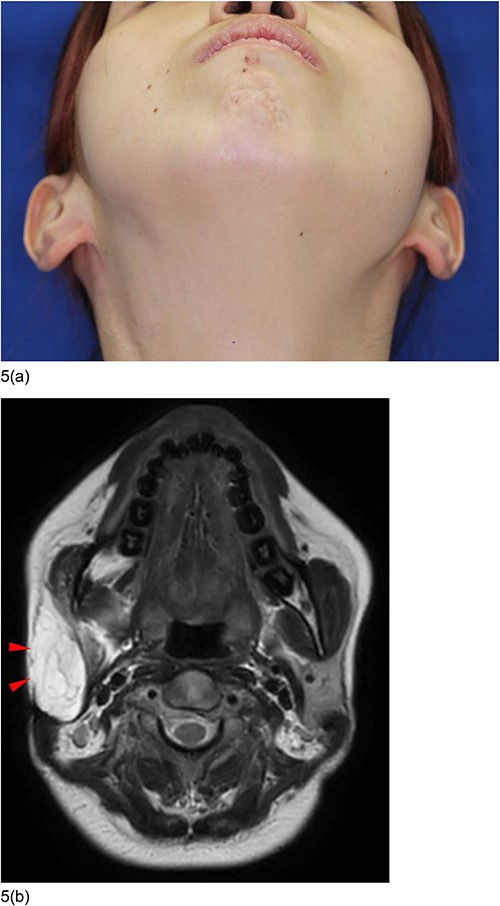

Six years following the second surgery, the concave deformity had significantly improved, restoring symmetrical facial contours (Fig. 5a).

Postoperative condition 6 years after the second surgery. (a) The concave deformity was improved and the facial contours became symmetrical. (b) MRI images showed that the concave deformed area was filled with fat of the flap (triangles).

Notably, there were no complications such as facial nerve paralysis or Frey syndrome. MRI showed that the concave, deformed area was filled with fat from the flap (Fig. 5b).